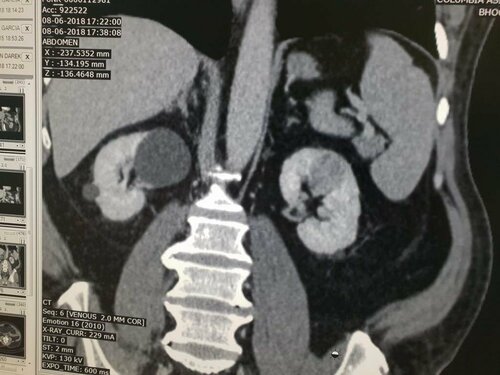

A  68 years old man came to best urologist in Pune, Dr. Bhoopat Bhati with pain in abdomen  post Angioplasty with Diabetes and Hyp...